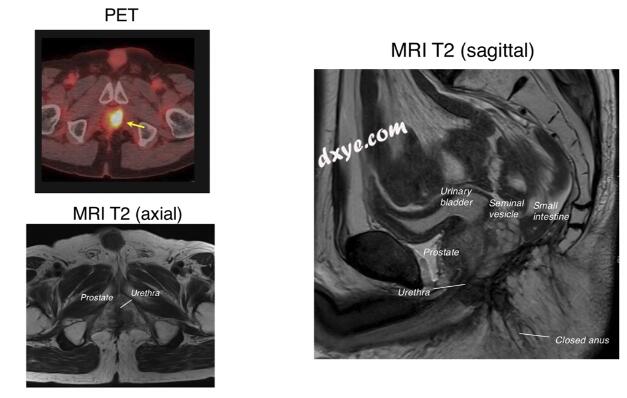

73 岁男性,BMI 24.3

局部复发肿瘤

- Rb 直肠癌

CRT

CPT-11+S1+长程放疗 (45Gy/25fr)

首次手术:机器人APR

ypT3 ypNO MO f第ll期,CRM:0.8 mm疗效:2级

10个月后

盆腔内局部复发